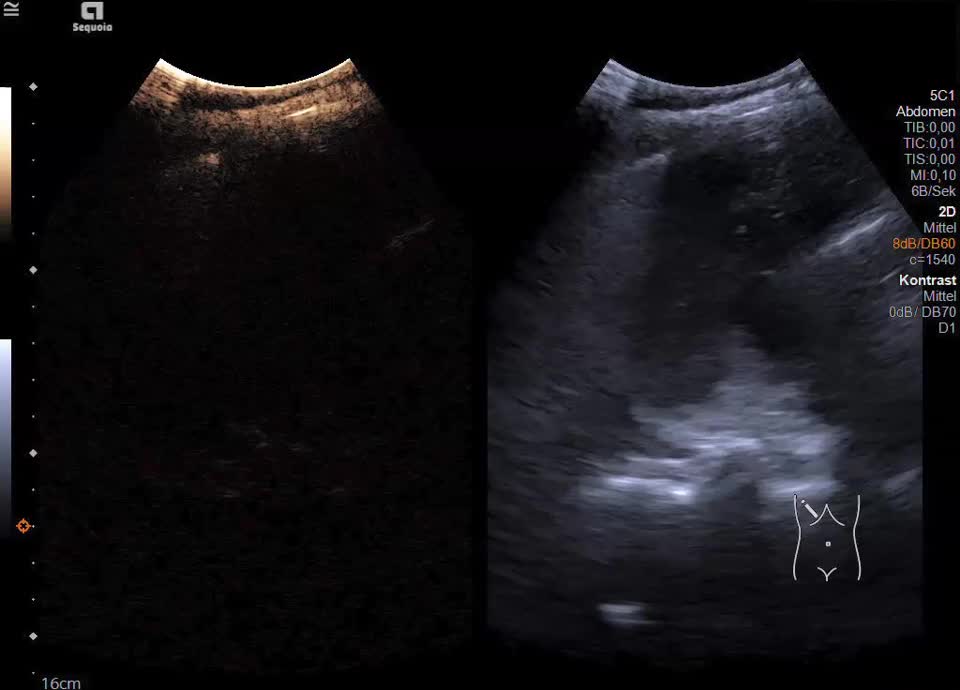

Es zeigt sich subkapsulär in Segment VI der Leber eine zystische Raumforderung mit durchgehendem Kapselreflex und hyperechogenem solidem Anteil. Der Befund ist nicht vereinbar mit einer blanden Zyste, sondern suspekt auf eine zystisch-solide Metastase. In der ergänzenden CEUS nehmen die soliden Anteile in der arteriellen Phase Kontrastmittel auf und zeigen in den portalvenösen sowie späten Phasen eine persistierende KM-Anreicherung ohne Washout. Zusätzlich finden sich eine noduläre Peritonealverdickung im Oberbauch sowie ein zystischer Ovarialtumor mit soliden Anteilen im rechten Unterbauch. In Zusammenschau der Befunde besteht der dringende Verdacht auf ein hepatisch und peritoneal metastasierendes Ovarialkarzinom.